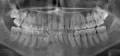

Сделав рентген, врач сказал, что требуется вмешательство стоматолога-хирурга. Так как 8-й зуб уперся в 7-й и именно это является причиной боли. С этим я с ним согласен. Но он сказал, что рано или поздно придется делать операцию и удалять 8-й зуб, так как он сам не прорастет. И главное он говорил, так как будто нет шансов, что зуб сам сможет прорасти.

Действительно, Ваш зуб самостоятельно прорезаться не может, потому что он "лежит" по направлению к 7-му зубу, самостоятельно он может двигаться только в сторону 7-го.